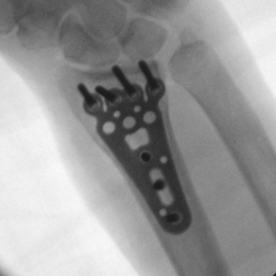

Röntgenbilder